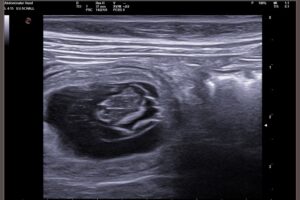

Endlich war es soweit, am 25. Februar 2026 konnten wir am späten Nachmittag mit Doria zur Ultraschalluntersuchung zum Tierarzt. Ich war den ganzen Tag schon etwas aufgeregt, obwohl Doria – genau wie beim A-Wurf – inzwischen schon sehr viele Anzeichen für eine erfolgreiche Trächtigkeit zeigte: – Futtermäkeligkeit– Absetzen von Schleim– ein etwas runderer Bauch Wir …